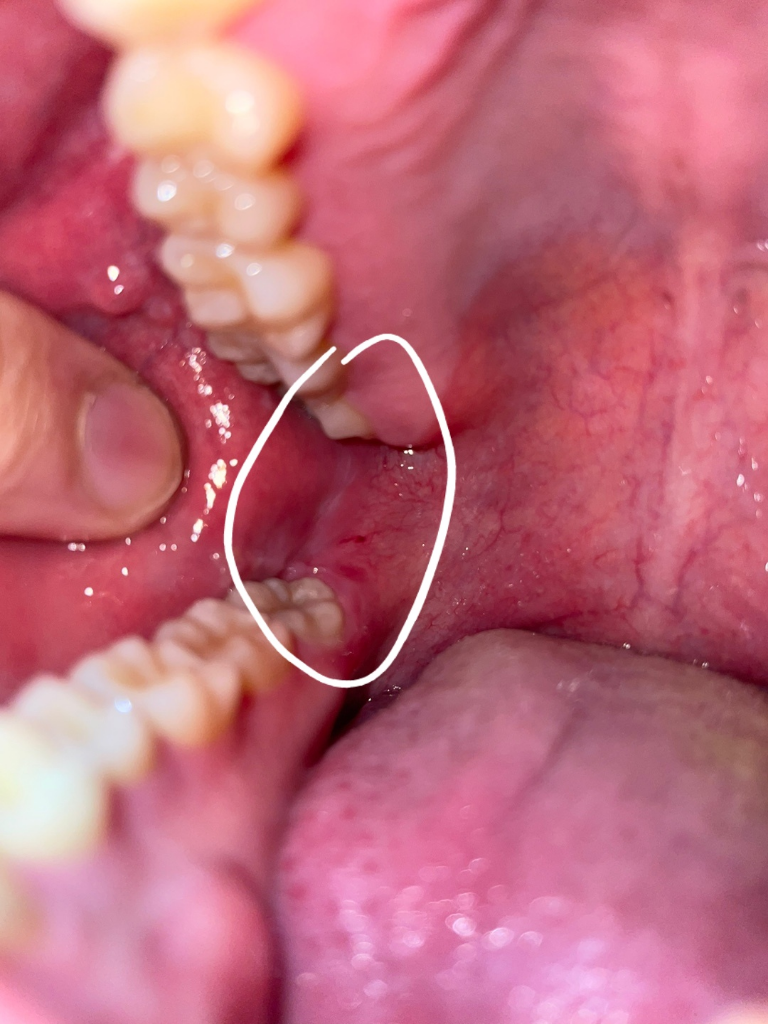

입안을 보던중 양쪽 어금니 안쪽 위치에 사진과 같이 하얀색 (연한 핑크?) 세로줄이 보여서 질문드립니다. 혹시 백반증인가 그건가요..? 양쪽에 있긴한데 한쪽이 조금더 넓게 보입니다 통증은 없어요

• 2번 째 사진

사랑니 때문에 잇몸이 부어서 그러기도 하고, 볼살이 치아에 씹혀서 그럴수도 있습니다. 문제가 잇는건 아닙니다.

1. 백반증은 구강암 전단계 병소인것은 맞습니다

2. 다만 사진상 나타난 양상은 백반증과는 다소 거리가있습니다

3. 악성병소(암)는 보통 경결감(딱딱함), 출혈, 궤양 등의 특징이 있습니다